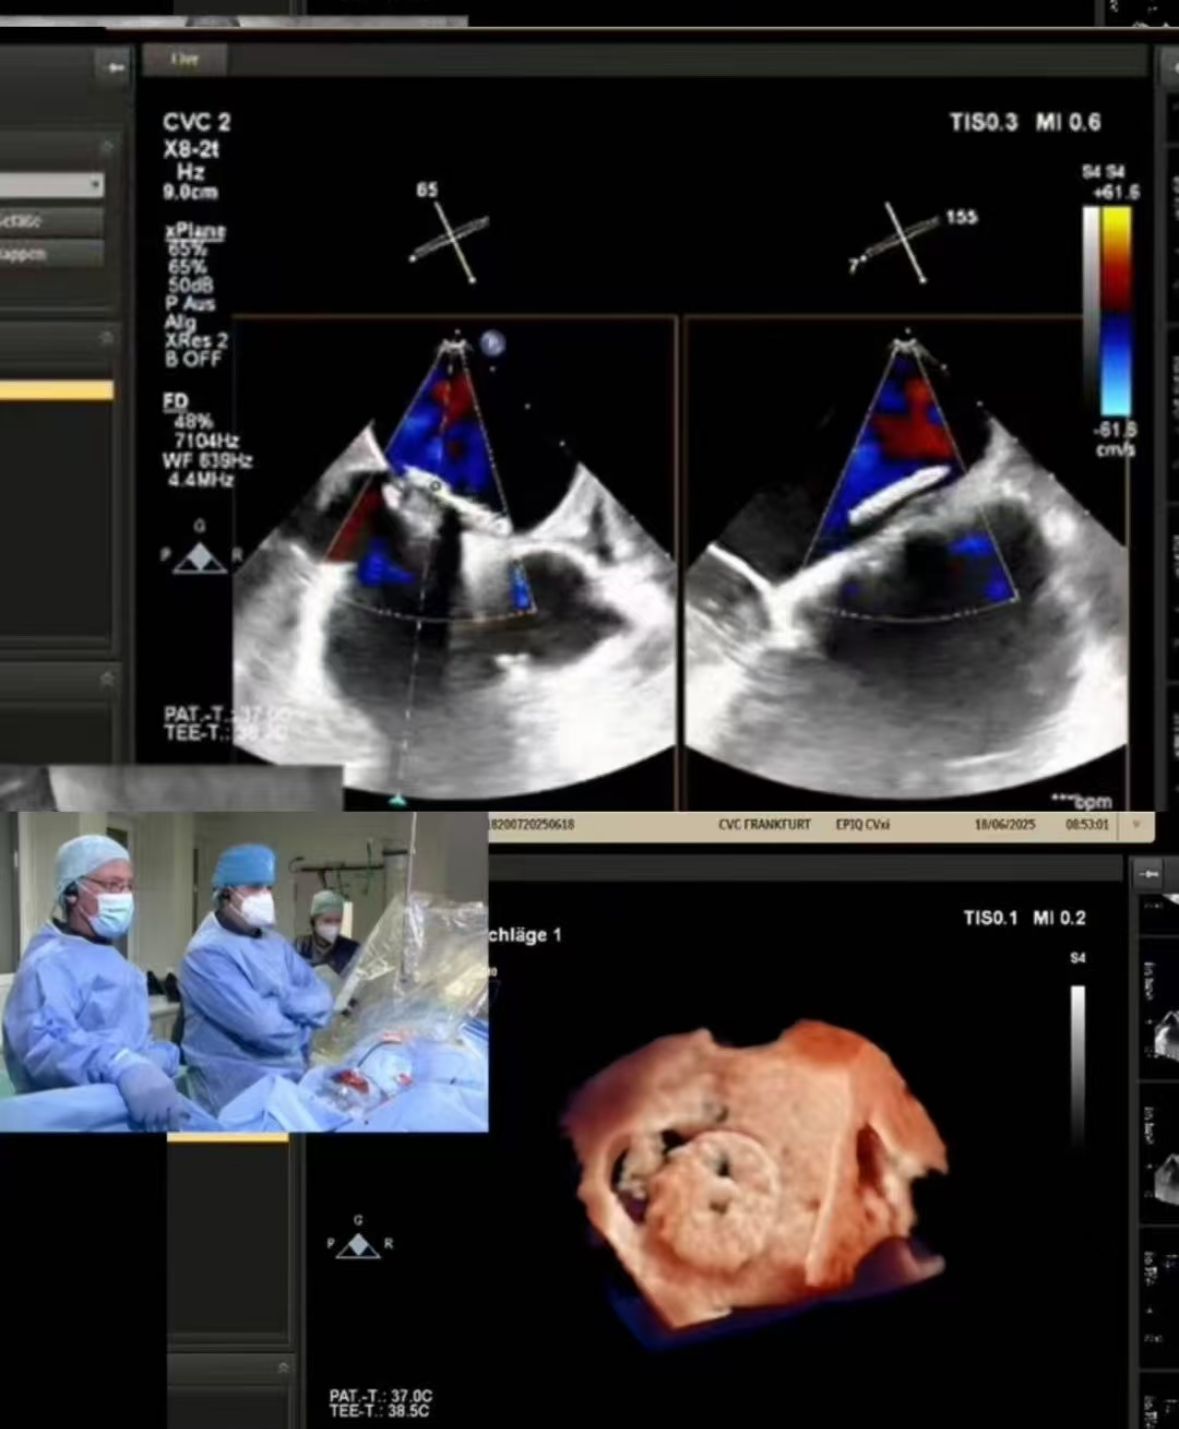

Thrilled to showcase our MemoSorb PFO Occluder – the world's first absorbable device (degrades to water & CO₂ within 1 year) – during a live broadcast from the Blue Room at CSI Frankfurt!

Wir haben eine komplexe PFO-Schließung gestreamt, die bei CVC Frankfurt an einer 60-jährigen Patientin durchgeführt wurde, mit:

1. Wiederkehrende Embolie-Striche (2014, 2021)

2. Schwere Nickel allergie (Kontraindikation für Metall geräte)

3. Residual Shunt nach vorheriger Schließung

2. Präzise Schließung: Echtzeit-Bildgebung führte zu einem perfekten Einsatz in heraus fordernder Anatomie (PFO-Tunnel fenes trier ung).